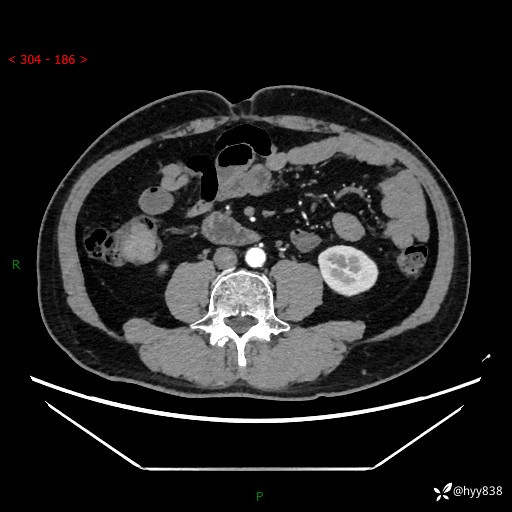

腹部CT增强扫描(外院CT平扫)

两期CT值:75hu 82hu